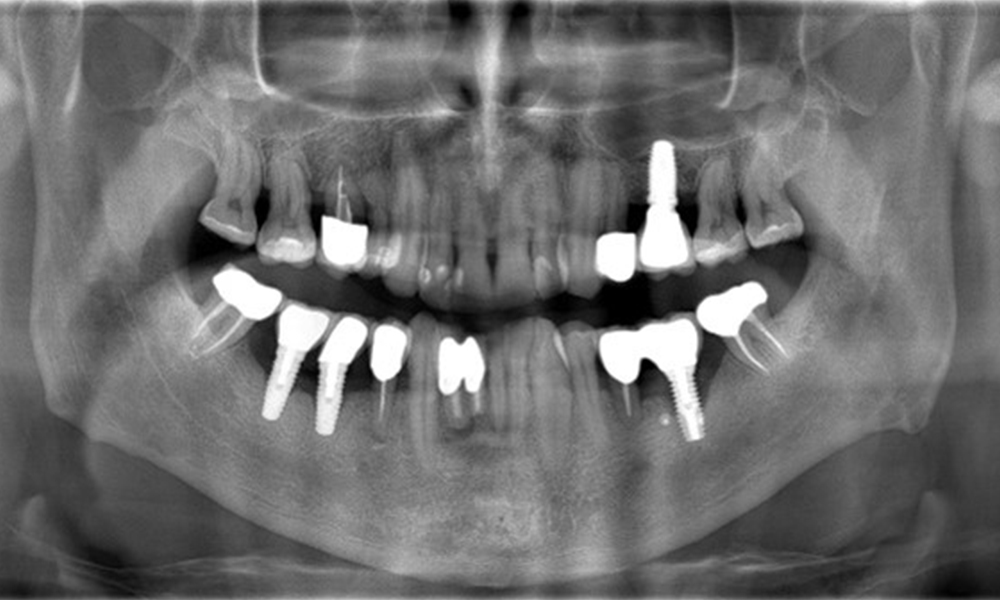

The X-ray images show the progression of bone loss.

The X-ray images show the progression of bone loss. OPG from 29.06.2020 (left) and OPG from 26.02.2024 (right).

OPG: 26/02/2024 Dental X-ray: 18/01/2024

The X-ray images show the progression of bone loss in the area of the implant in region 36: dental film from 11.02.2021 (left) and dental film from 18.01.2024 (right).